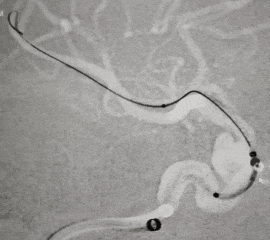

退支架外鞘管,将Surpass Streamline血流导向密网支架先释放到CAT 5里6-7mm

再退CAT5到外鞘管以下2mm,让支架锚定于远端。

固定支架外管,加力推支架内杆,增加系统张力将支架从外鞘管中推挤出来

支架没打开,只要大弯侧贴壁,就无需担心,持续保持张力推挤支架直至完全释放,再拉内杆减张,CAT5爬回远端。

由于回拉内杆减张动作较缓,没有给与支架小弯侧足够外力,支架没有完全贴壁,用导丝和CAT5按摩。

按摩后支架近端及中段小弯侧贴壁满意。